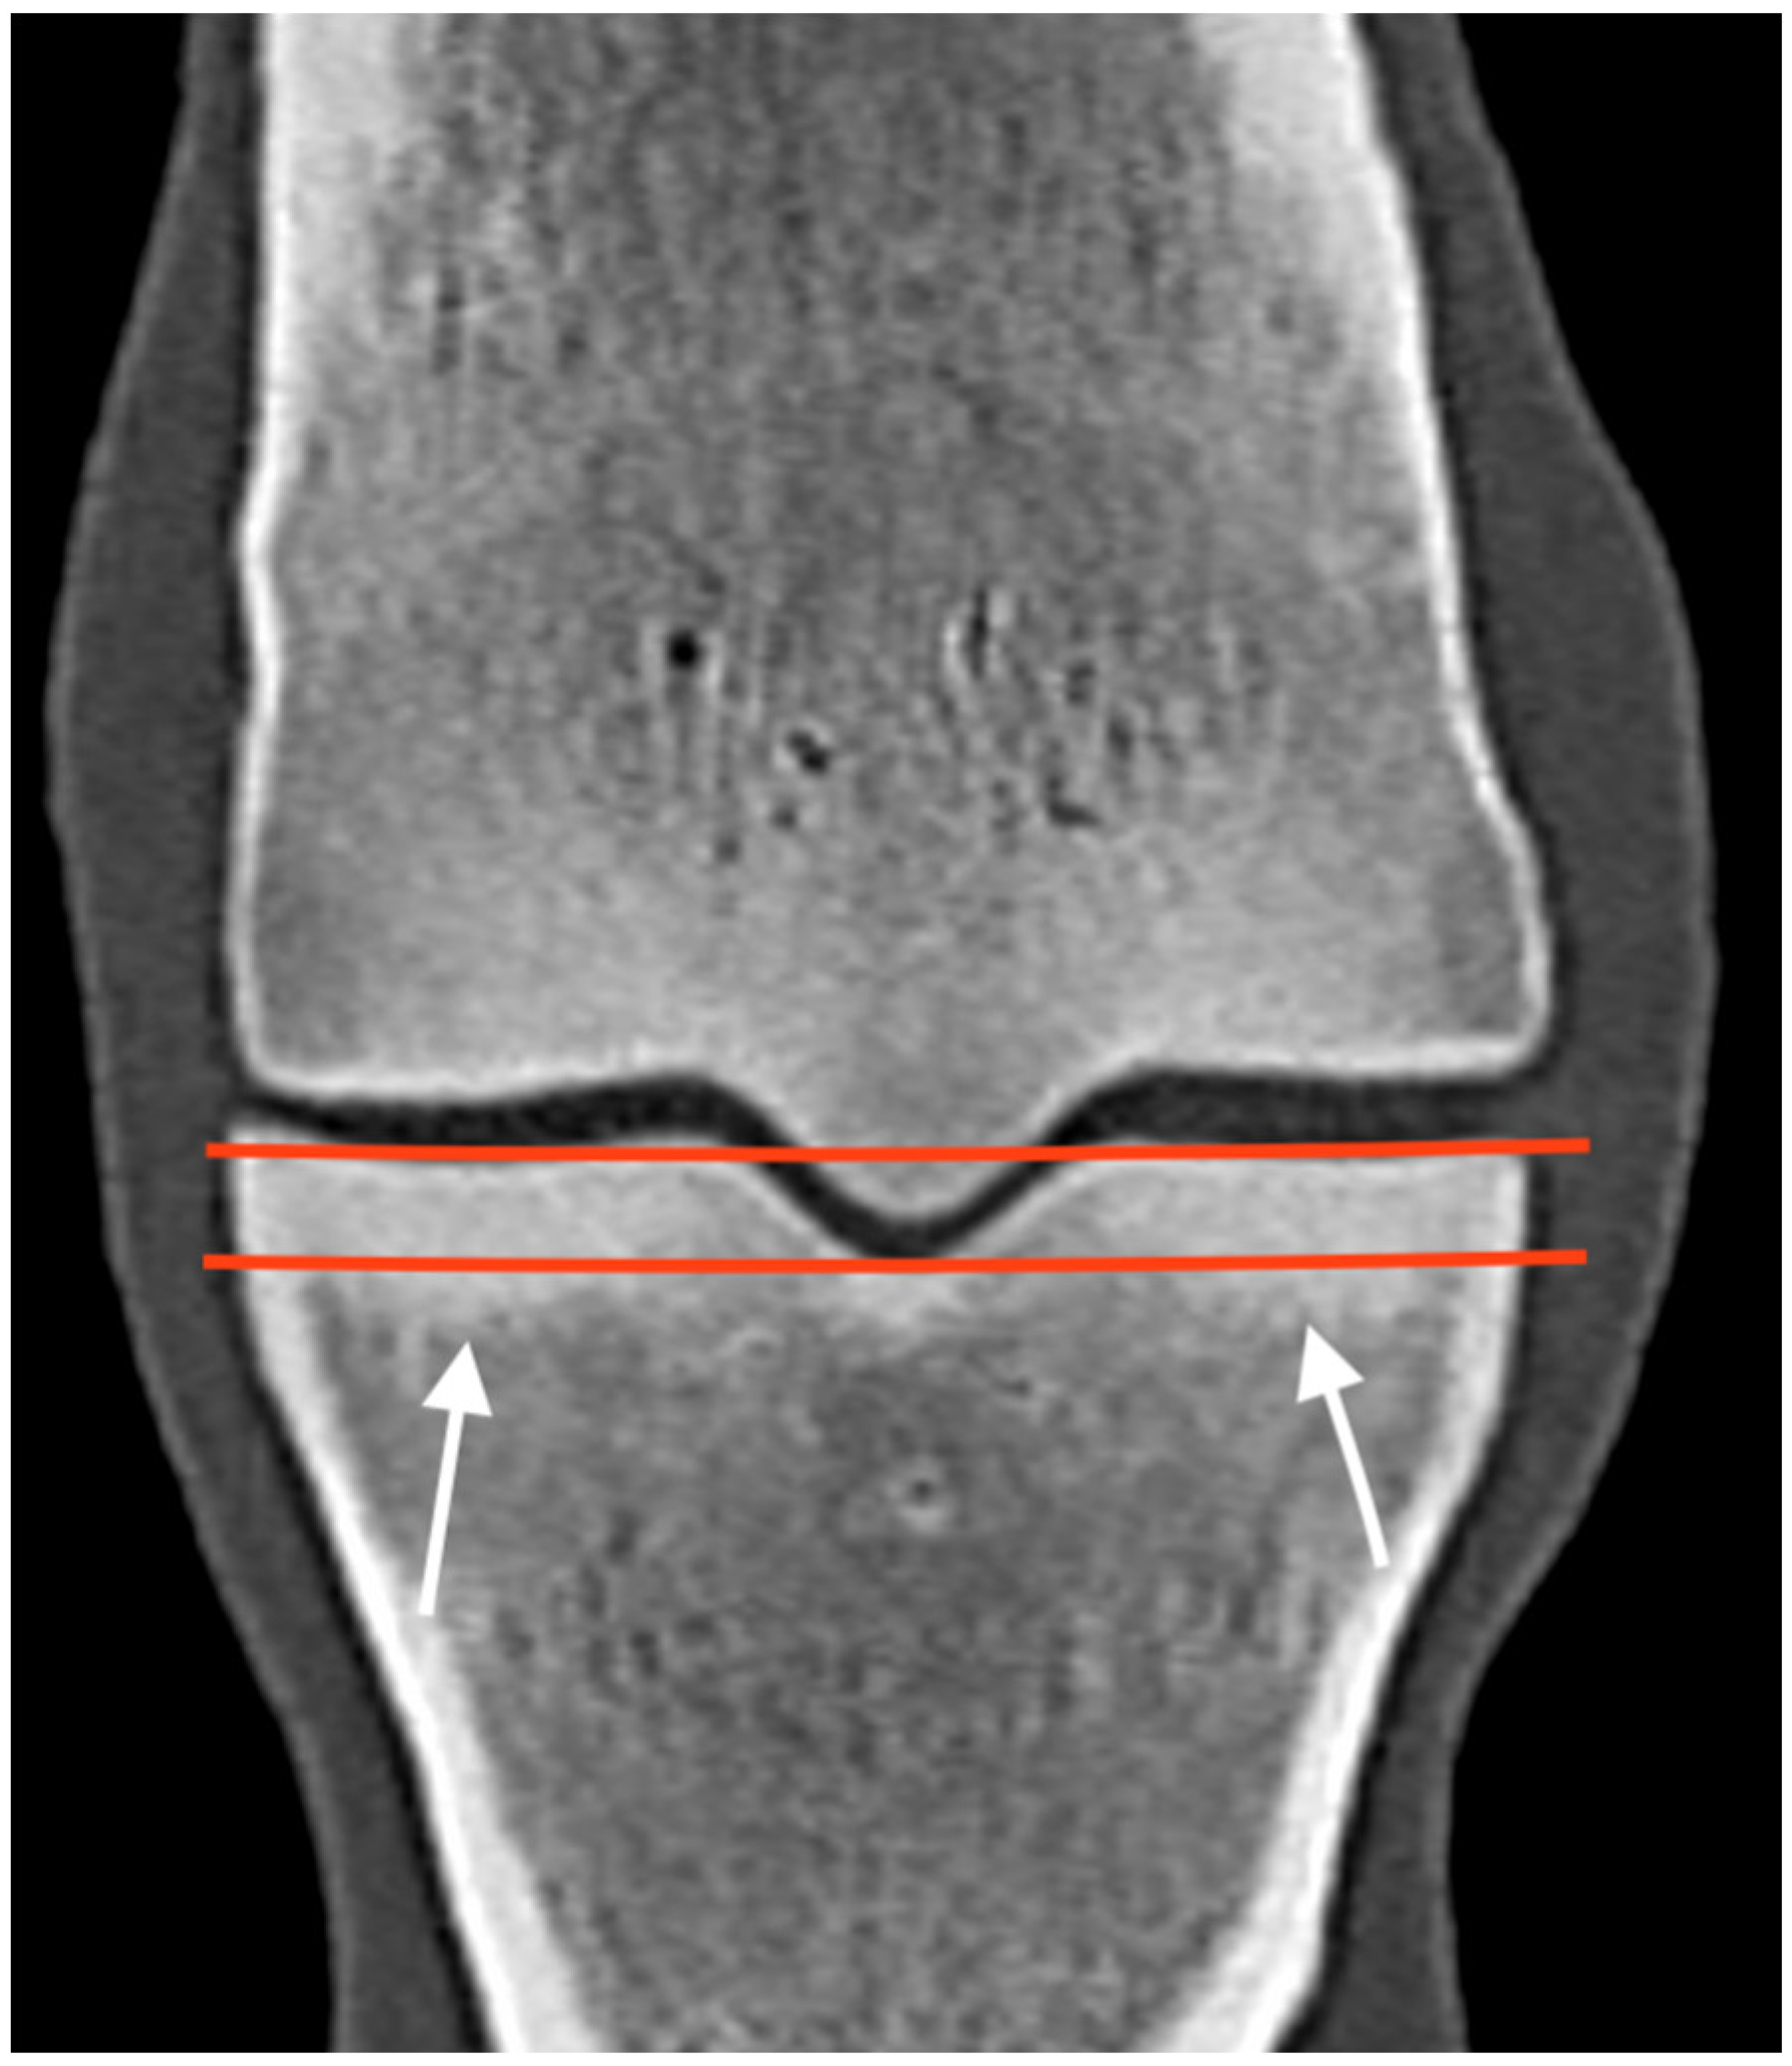

3.1. The Third Metacarpal Bone (McIII)

| Hypoattenuating lesion in the dorsal subchondral bone Subchondral bone thickening Dorsal/palmar half Increased attenuation in the trabecular bone Dorsal/palmar half Cone shaped/patchy Focal separated hyperattenuation | Hyperintense signal in the dorsal subchondral bone Subchondral bone thickening Dorsal/palmar half Decreased signal intensity in the trabecular bone Dorsal/palmar half Cone shaped/patchy Focal separated intermediate/low signal intensity | Radiolucent lesion Subchondral bone thickening Dorsal Increased trabecular bone opacity | |